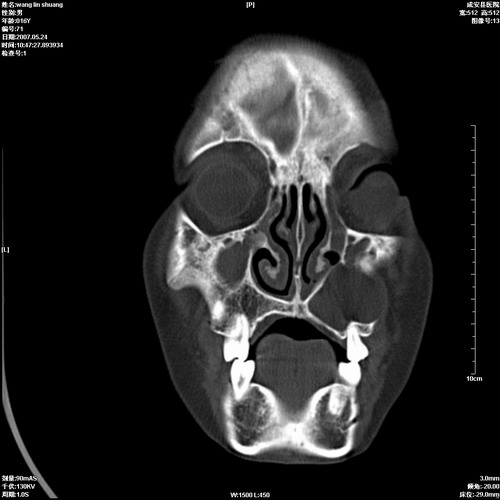

病人,男 16岁,鼻旁右肿胀,其余无不适感,ct图片

1、典型右侧根尖囊肿。

2、双侧上颌窦、筛窦、蝶窦炎

1\\左侧上颌骨含牙囊肿

2\\两上颌窦炎

右侧上颌骨含牙囊肿.双侧上颌窦炎症.

右侧上颌骨含牙囊肿.双侧上颌窦、蝶窦右侧炎症.

1、左侧上颌骨含牙囊肿。

典型的右侧上颌骨含牙囊肿,双侧上颌窦、右侧蝶窦炎症。

右侧上颌骨含牙囊肿,全组鼻窦炎